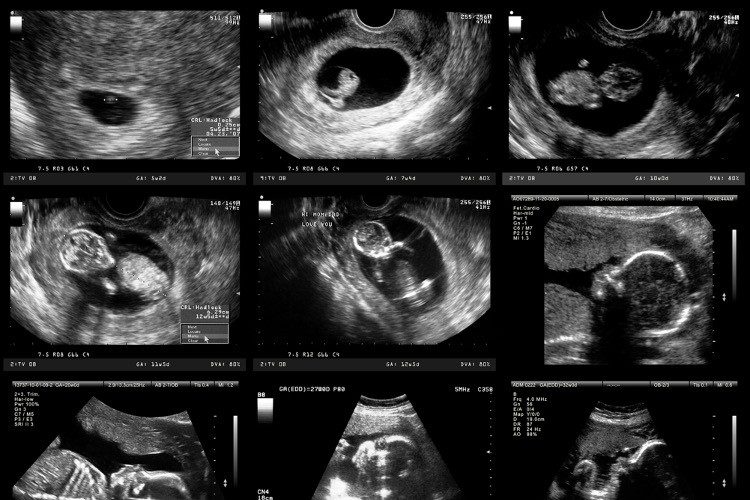

CNN reports that Florida House Bill 167, filed by Florida State Representative Webster Barnaby, prohibits abortions after a fetal heartbeat is detected, typically around six weeks into the pregnancy, with exceptions for rape, incest, domestic violence, human trafficking, or a life-threatening condition. It allows private citizens to bring lawsuits against physicians who provide abortions after six weeks. Under the measure, lawsuits can be brought against any person who “knowingly engages in conduct that aids or abets the performance or inducement of an abortion.” The Florida bill allows lawsuits up to six years after the law has been violated, differing slight from the Texas law, which creates a four-year window. Notably, the bill also removes the word “fetus” from the language and replaces it with “unborn child.”

The act states, “a fetal heartbeat is a key medical predictor that an unborn child will reach live birth, and cardiac activity begins at a biologically identifiable moment in time, normally when the fetal heart is formed in the gestational sac…. The State of Florida has a compelling interest from the outset of a woman’s pregnancy in protecting the health of the woman and the life of the unborn child, and in order to make an informed choice about whether to continue her pregnancy, the pregnant woman has a compelling interest in knowing the likelihood of her unborn child surviving to full-term birth based upon the presence of cardiac activity.”